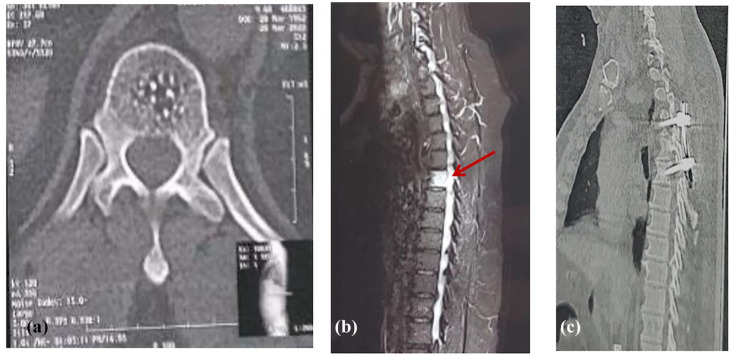

脊索瘤是一种生长缓慢、局部浸润性的低级别肿瘤,属于肉瘤家族。它主要侵犯骶骨和颅底。我们报告了一例最初表现为硬膜外血肿(EDH)的胸脊索瘤病例,这是一种罕见的临床实体瘤。我们在报告该病例的同时,还对文献中的类似病例进行了PRISMA驱动的系统综述。该综述包括胸椎脊索瘤的临床特征和预后。我们的病例涉及一名 60 岁的男性,尽管他没有外伤史,但却出现了急性截瘫。在 T6 水平发现硬膜外血肿,因此进行了 T4-6 椎板切除和固定手术。手术后六个月,患者下肢逐渐出现无力和痉挛。计算机断层扫描(CT)显示,T6受到侵蚀,并伴有侵袭性肿块。磁共振成像(MRI)显示,D6的椎体和右侧椎弓根处有一个巨大的异质软组织肿块,突出于硬膜外腔,并在该水平压迫脊髓。肿块大小约为 5 × 4 × 3.5 厘米。磁共振脊髓造影显示,T5-6水平有充盈缺损,证实软组织病变位于椎管内。完全切除肿块后,确诊为胸脊索瘤。术后随访显示,患者的下肢痉挛和截瘫症状明显改善,并开始接受辅助放疗。本病例强调了在评估类似 EDH 的表现时保持高度怀疑的重要性。

A chordoma is a slow growing, locally invasive, low-grade tumor belonging to the sarcoma family. It mainly affects the sacrum and skull base. We present a case of thoracic chordoma initially presented with epidural hematoma (EDH), which is a rare clinical entity. We reported this case, and also performed a PRISMA-driven systematic review to summary the similar cases in the literature. This review includes the clinical characteristics and outcome of thoracic chordoma. Our case involves a 60-year-old male who, despite no history of trauma, presented with acute paraparesis. An epidural hematoma was identified at T6 level, leading to a surgical intervention involving T4-6 laminectomy and fixation. Six months subsequent to surgery, the patient experienced progressive lower limb weakness and spasticity. Computed tomography (CT) exhibited erosion of T6 and an associated aggressive mass. Magnetic resonance imaging (MRI) revealed a large heterogenous soft tissue mass arising from the vertebral body and right pedicle of D6, protruding in the epidural space and compressing the spinal cord focally at this level. The mass measured approximately 5 × 4 × 3.5 cm. Magnetic resonance myelography indicated a filling defect at T5-6 level, confirming the intraspinal location of the soft tissue lesion. Complete excision of the mass confirmed the diagnosis of thoracic chordoma. Postoperative follow-up demonstrated notable improvement in the lower limb spasticity and paraparesis, and the patient started adjuvant radiotherapy. This case underscores the importance of maintaining a high index of suspicion when evaluating presentations resembling EDH.